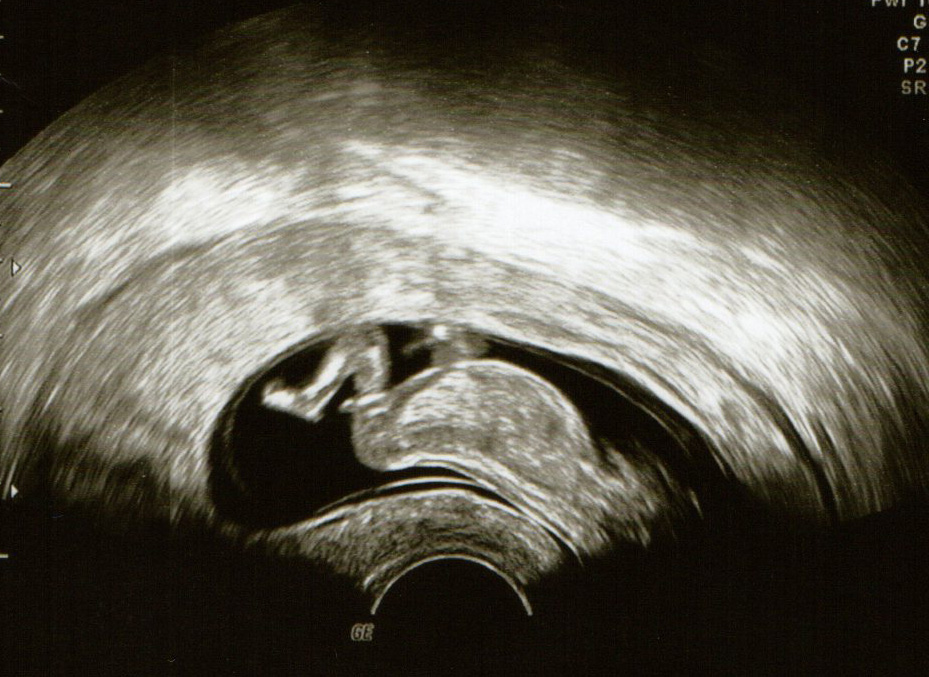

I wondered if you could all take a look at my nub pictures from 12+1. All but one of them seem to look flat and the one that is sticking up a little bit doesn't seem to be a very good pic at all? Thanking you all in advance!

Attachment 12792Attachment 12790Attachment 12791Attachment 12793